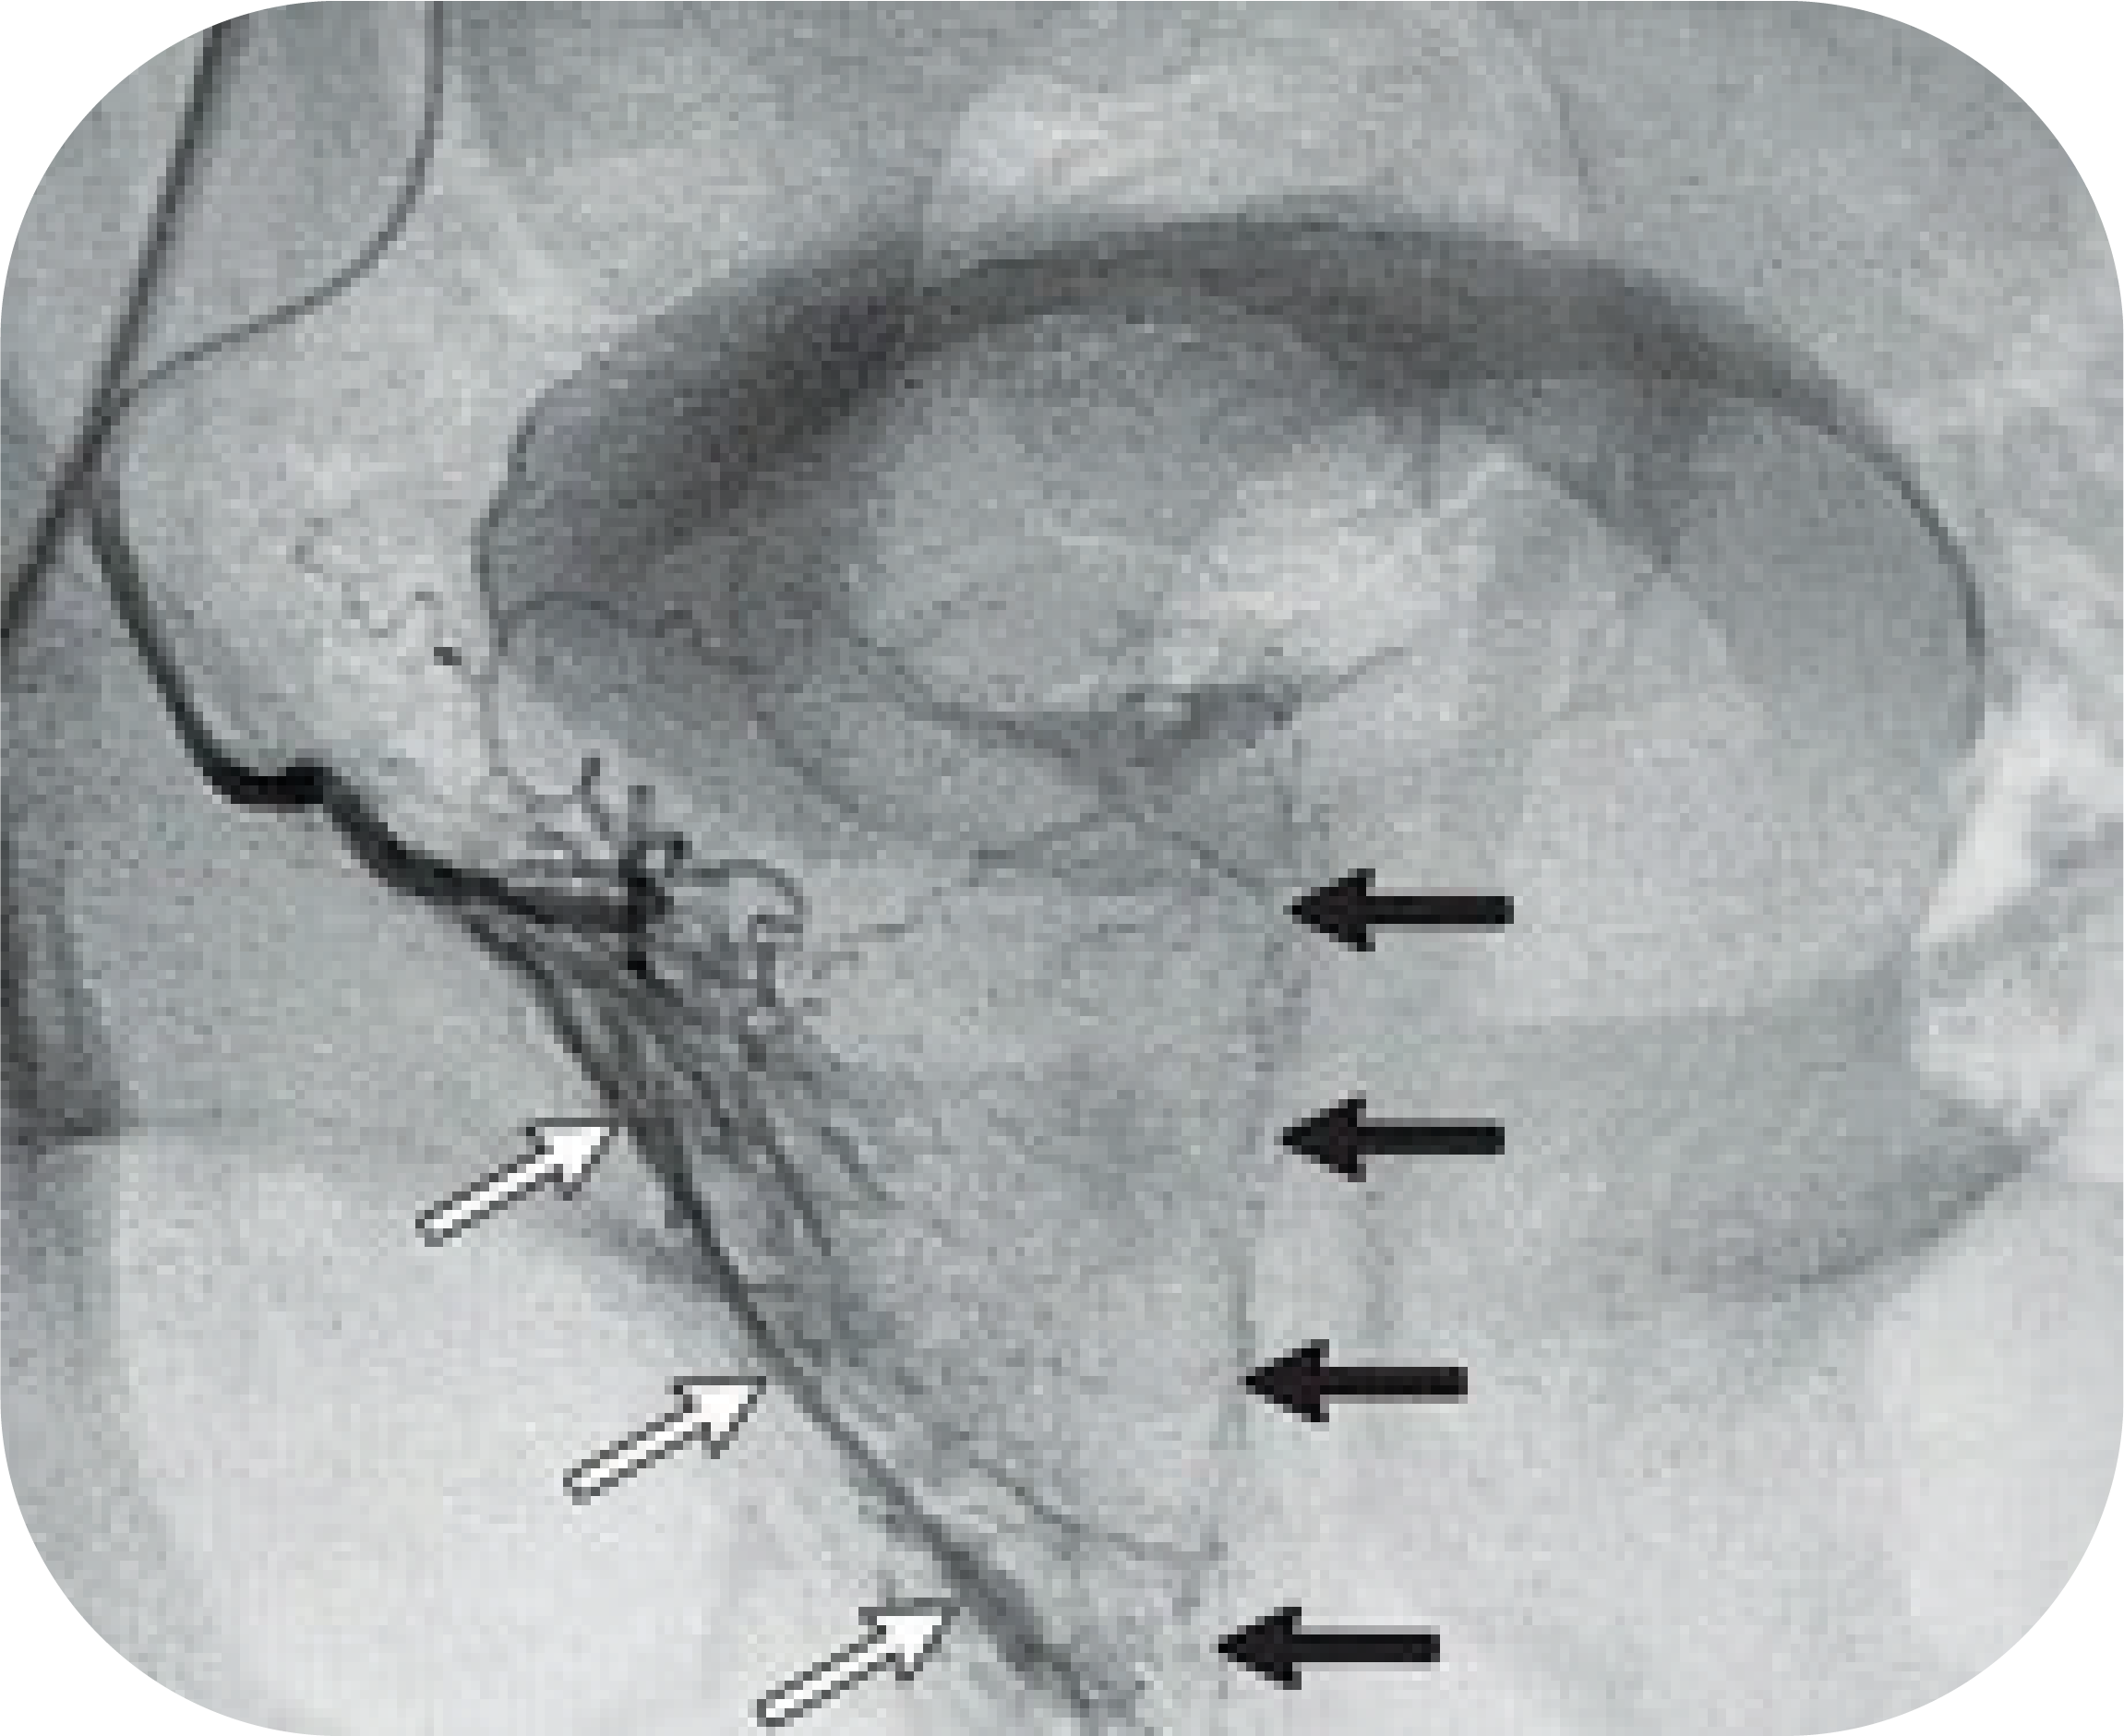

Эмболизация простатических

Эмболизация простатических 111 фото